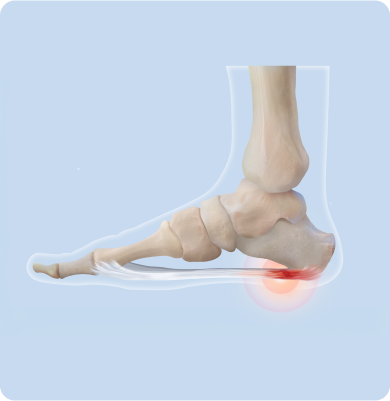

발뒤꿈치에서 발바닥 앞쪽까지 이어진 족저근막에 염증이 생기는 질환

장시간 서 있거나 오래 걷는 생활습관, 딱딱한 바닥에서의 활동, 발에 맞지 않는 신발 착용, 과체중, 아치 변형 등으로 족저근막에 반복적인 스트레스가 가해져 발생합니다.